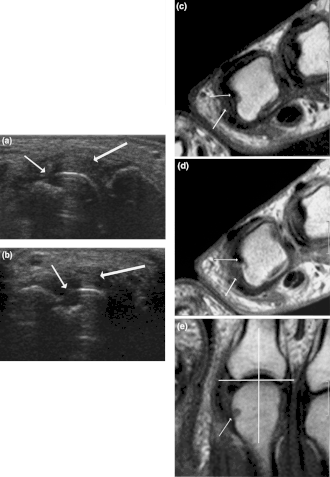

| Sinovite de terceiro grau na segunda articulação metacarpo-falângica (infecção na base do dedo indicador). | |

A sinovite subclínica pode ser detectada por ressonância magnética (MRI). As sinovites crônicas podem resultar em degeneração da articulação.